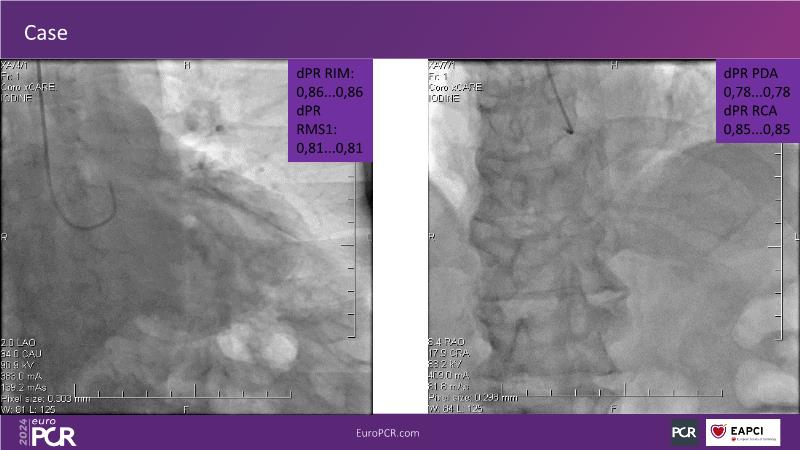

Follow this session to discover how accurate resting index can inform decision-making for DCB in CTO patients and understand the role of physiology in a new PCI workflow for complex MVD. Thus, you will learn about a DCB intention-to-treat strategy guided by post-PCI coronary physiology in complex lesions, review new procedural techniques and workflows from real-world cases, and explore the pros and cons of this novel approach.

- To learn about DCB intention-to-treat strategy guided by post-PCI coronary physiology in complex lesions

- To review new procedural technique and workflow from real world patient cases